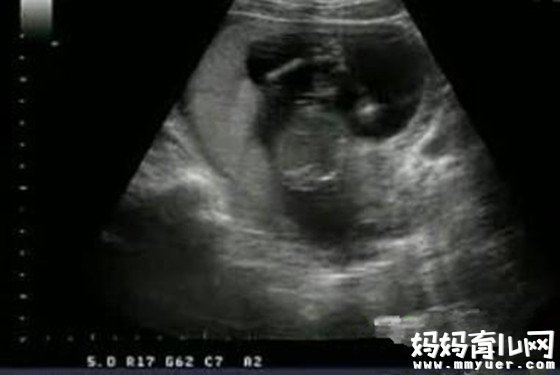

怀孕四个月男胎儿图

现在胎儿的生殖器官已经形成,用B超可以分辨出胎儿的性别了,你一定想知道是男孩还是女孩,但一般来讲男孩和女孩各占一半,男孩略多些。一般情况下,国内的性别检查,只用于判断某些通过性别遗传的疾病检测。

b超看胎儿性别是男孩/女孩生殖器的发育是个逐步的过程。只有从你怀孕11周(80天)左右开始,不同性别的胎儿外表上才开始显现出差异。在这个时候,所有胎儿的生殖器部位都有个突出。对于男孩,这个突出往往是伸向上方,和脊柱之间的夹角大于30°。相比较而言女孩生殖器的突出方向会显得水平一些,和脊柱之间的夹角小于30°。

胎儿发育:胎儿现在的身长大约12厘米,体重达到了150克,大小正好可以放在你的手掌里。他/她自己会在子宫中玩脐带,可以不断的吸入和呼出羊水了。更令人惊喜的是,在宝宝16周的时候你对胎动的感觉更加明显,有时还会有些触痛感,这些都是正常的反应。他/她的生殖器官已经形成,通过B超可以分辨出胎儿的性别。